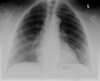

Findings?

Diagnosis?

-Dx if HLA-B27 is (-)

Bilateral Sacroilitis

Dx is seronegative arothropathies like AS or Enteropathic Arthritis

if HLA-B27 is (-), then it could be caused by Gout if uric acid levels are high